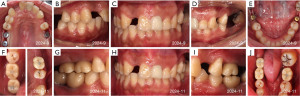

A 27-year-old woman with a childhood history of poliomyelitis presents at the Affiliated Stomatological Hospital of Zhejiang University. She understands sample instructions but cannot clearly express needs, has multiple caries-induced missing teeth affecting eating, and seeks chewing function restoration. The patient exhibits facial asymmetry, deviated mouth corners, and leftward mandibular movement on opening. She also displays asymmetric paralysis, muscle atrophy, and joint deformities (Figure 1). Intraoral examination discloses dentition defects of both arches (#16, #17, #12, #24, #26, #27, #36, #37, #46, #47) (Figure 2). Preoperative cone-beam computed tomography (CBCT) imaging indicates inadequate height of the maxillary alveolar bone (about 8 mm), with adequate quantity of the mandibular bone (Figure 3).

The entire surgical procedure is completed within 90 minutes, and the postoperative CBCT scan indicates proper implant positioning without damage to critical structures (Figure 4). The mesiodistal distances are adequate, all measuring over 1.5 cm; however, the buccolingual bone plate width is suboptimal, ranging from 1.2 to 2 cm, possibly influenced by artifacts from the implant. No significant complications were noted during and after the procedure. Six months postoperatively, the patient returns for follow-up and undergoes second-stage surgery. The implant site shows excellent healing. After removing the cover screws, healing abutments are placed (Figure 5). The digital scan is performed to create a three-dimensional (3D) model due to the patient’s poor cooperation with traditional impressions (Figure 6). A monolithic zirconia crown, known for its high elastic modulus and biomedical compatibility, is selected. Given the patient’s limited inter-arch space, the neck design is extended subgingivally, with grooves added to the sandblasted abutment surface. On the patient’s right side, a conservative occlusal design is implemented to mitigate occlusal forces. This involves the maintenance of a residual gap between #36 and #38, in addition to a reduction of the apical bevel slope and crowns for #36 and #46. The patient’s response to the restoration is carefully monitored. Once confirmed in position, the screw access holes are sealed, completing the permanent restoration (Figure 5). The patient and family are instructed on hygiene practices to maintain proper oral hygiene and advised to return for regular follow-ups. At the 4-month follow-up, the oral examination shows secure implant retaining screws. Peri-implant soft tissues exhibit favorable morphology, and occlusal relationships remain consistent (Figure 7). The family reports significant improvement in masticatory function, with no abnormal reactions to daily foods.